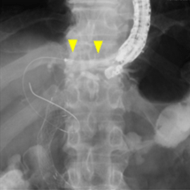

超音波内視鏡下胆道ドレナージ術(EUS-BD)

ERCPによる経乳頭的な胆道ドレナージが困難な場合に胃あるいは十二指腸から胆管を穿刺し、 ステントを留置します。従来のPTBD(経皮経肝的胆道ドレナージ)と比較して、チューブが 体外に出ることがなく、金属ステントを用いることで長期間のステント開存が期待できます。

胃から肝臓内の胆管に金属ステントを留置しています

超音波内視鏡で肝臓内の胆管を穿刺しています